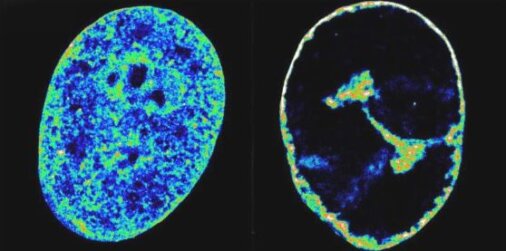

Το ανθρώπινο DNA στη φυσική του κατάσταση μέσα στα κύτταρα (αριστερά) σε σύγκριση με οκτώ ώρες μετά τη μόλυνση με HSV-1 (δεξιά). Ο ιός συμπιέζει σημαντικά το μέγεθος του ανθρώπινου γονιδιώματος και το μετακινεί προς την άκρη του πυρήνα, ελευθερώνοντας χώρο για να δημιουργήσει ένα εργοστάσιο για τους δικούς του σκοπούς. Πίστωση: Esther Gonzalez Almela και Álvaro Castells García

Τρεις ώρες μετά τη μόλυνση, το μεγαλύτερο μέρος της πολυμεράσης και ένα σημαντικό κλάσμα των άλλων δύο παραγόντων είχαν εγκαταλείψει τα ανθρώπινα γονίδια. Η μαζική κλοπή προκαλεί την κατάρρευση της μεταγραφής στο γονιδίωμα του ξενιστή, η οποία με τη σειρά της προκάλεσε τη σύνθλιψη της χρωματίνης, της φυσικής κατάστασης του ανθρώπινου γονιδιώματος μέσα στα κύτταρα, σε ένα πυκνό κέλυφος μόλις 30% του αρχικού του όγκου. Αυτό ήταν ένα απροσδόκητο εύρημα.